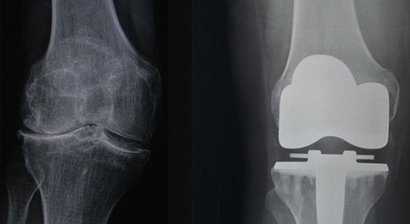

Im Falle einer notwendigen Operation wird diese von mir im Evangelischen Krankenhaus Wien durchgeführt. Meine chirurgischen Schwerpunkte liegen im künstlichen Gelenkersatz , in der Fußchirurgie und den arthroskopischen Operationstechniken.

Ich habe mich auf die Implantation von künstlichen Knie- und Hüftgelenken spezialisiert und setze hier auf monderne minimalinvasive und schonende Operationstechniken (AMIS-Methode).

Künstliches Kniegelenk